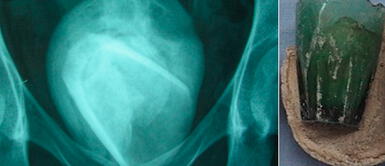

Supuestamente, la atención médica se iba a dar por una infección urinaria. Luego de varios estudios, los doctores del Hospital Académico Habib Bourguiba llegó a la conclusión que la paciente tenía un vaso de vidrio dentro de su vejiga, por más de cuatro años, según informó el propio New York Times.

En dicho tiempo, el vaso fue cubierto por un cálculo vesical de 8 cm de ancho, que se formó tras insertarse el objeto en la uretra.

La paciente se quejó de síntomas de infección urinaria y en los primeros análisis no arrojó nada similar. Sin embargo, lo que llamó la atención fue la elevada cantidad de globulos rojos. Por eso, los médicos descubrieron que tenía cálculos en la vejiga, que indicó lucha contra la infección.